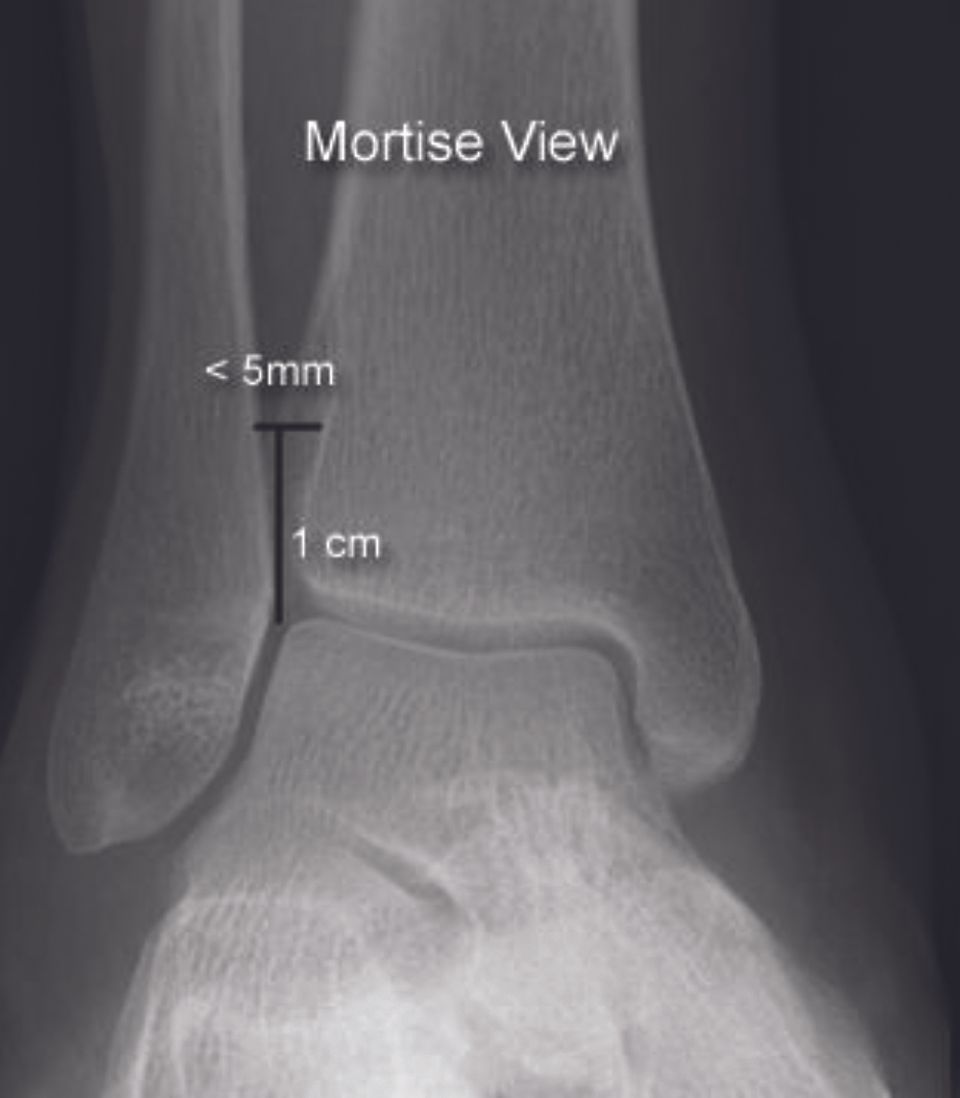

Radiographs (Figure 9)

Standard x-rays (AP/mortise and lateral) of the ankle are generally used to rule out malleolar fractures. A useful tool in detecting syndesmotic diastasis may be the evaluation of the space between tibia and fibula, measured on the injured and healthy side. With syndesmotic instability, the clear space widens (diastasis) while the overlap is reduced. Generally, a tibiofibular clear space of less than 6 mm in the mortise view is considered normal [26] In a systematic review looking at accuracy of imaging, the pooled sensitivity for X-ray was 0.53 and the specificity was 0.98 respectively. [27]